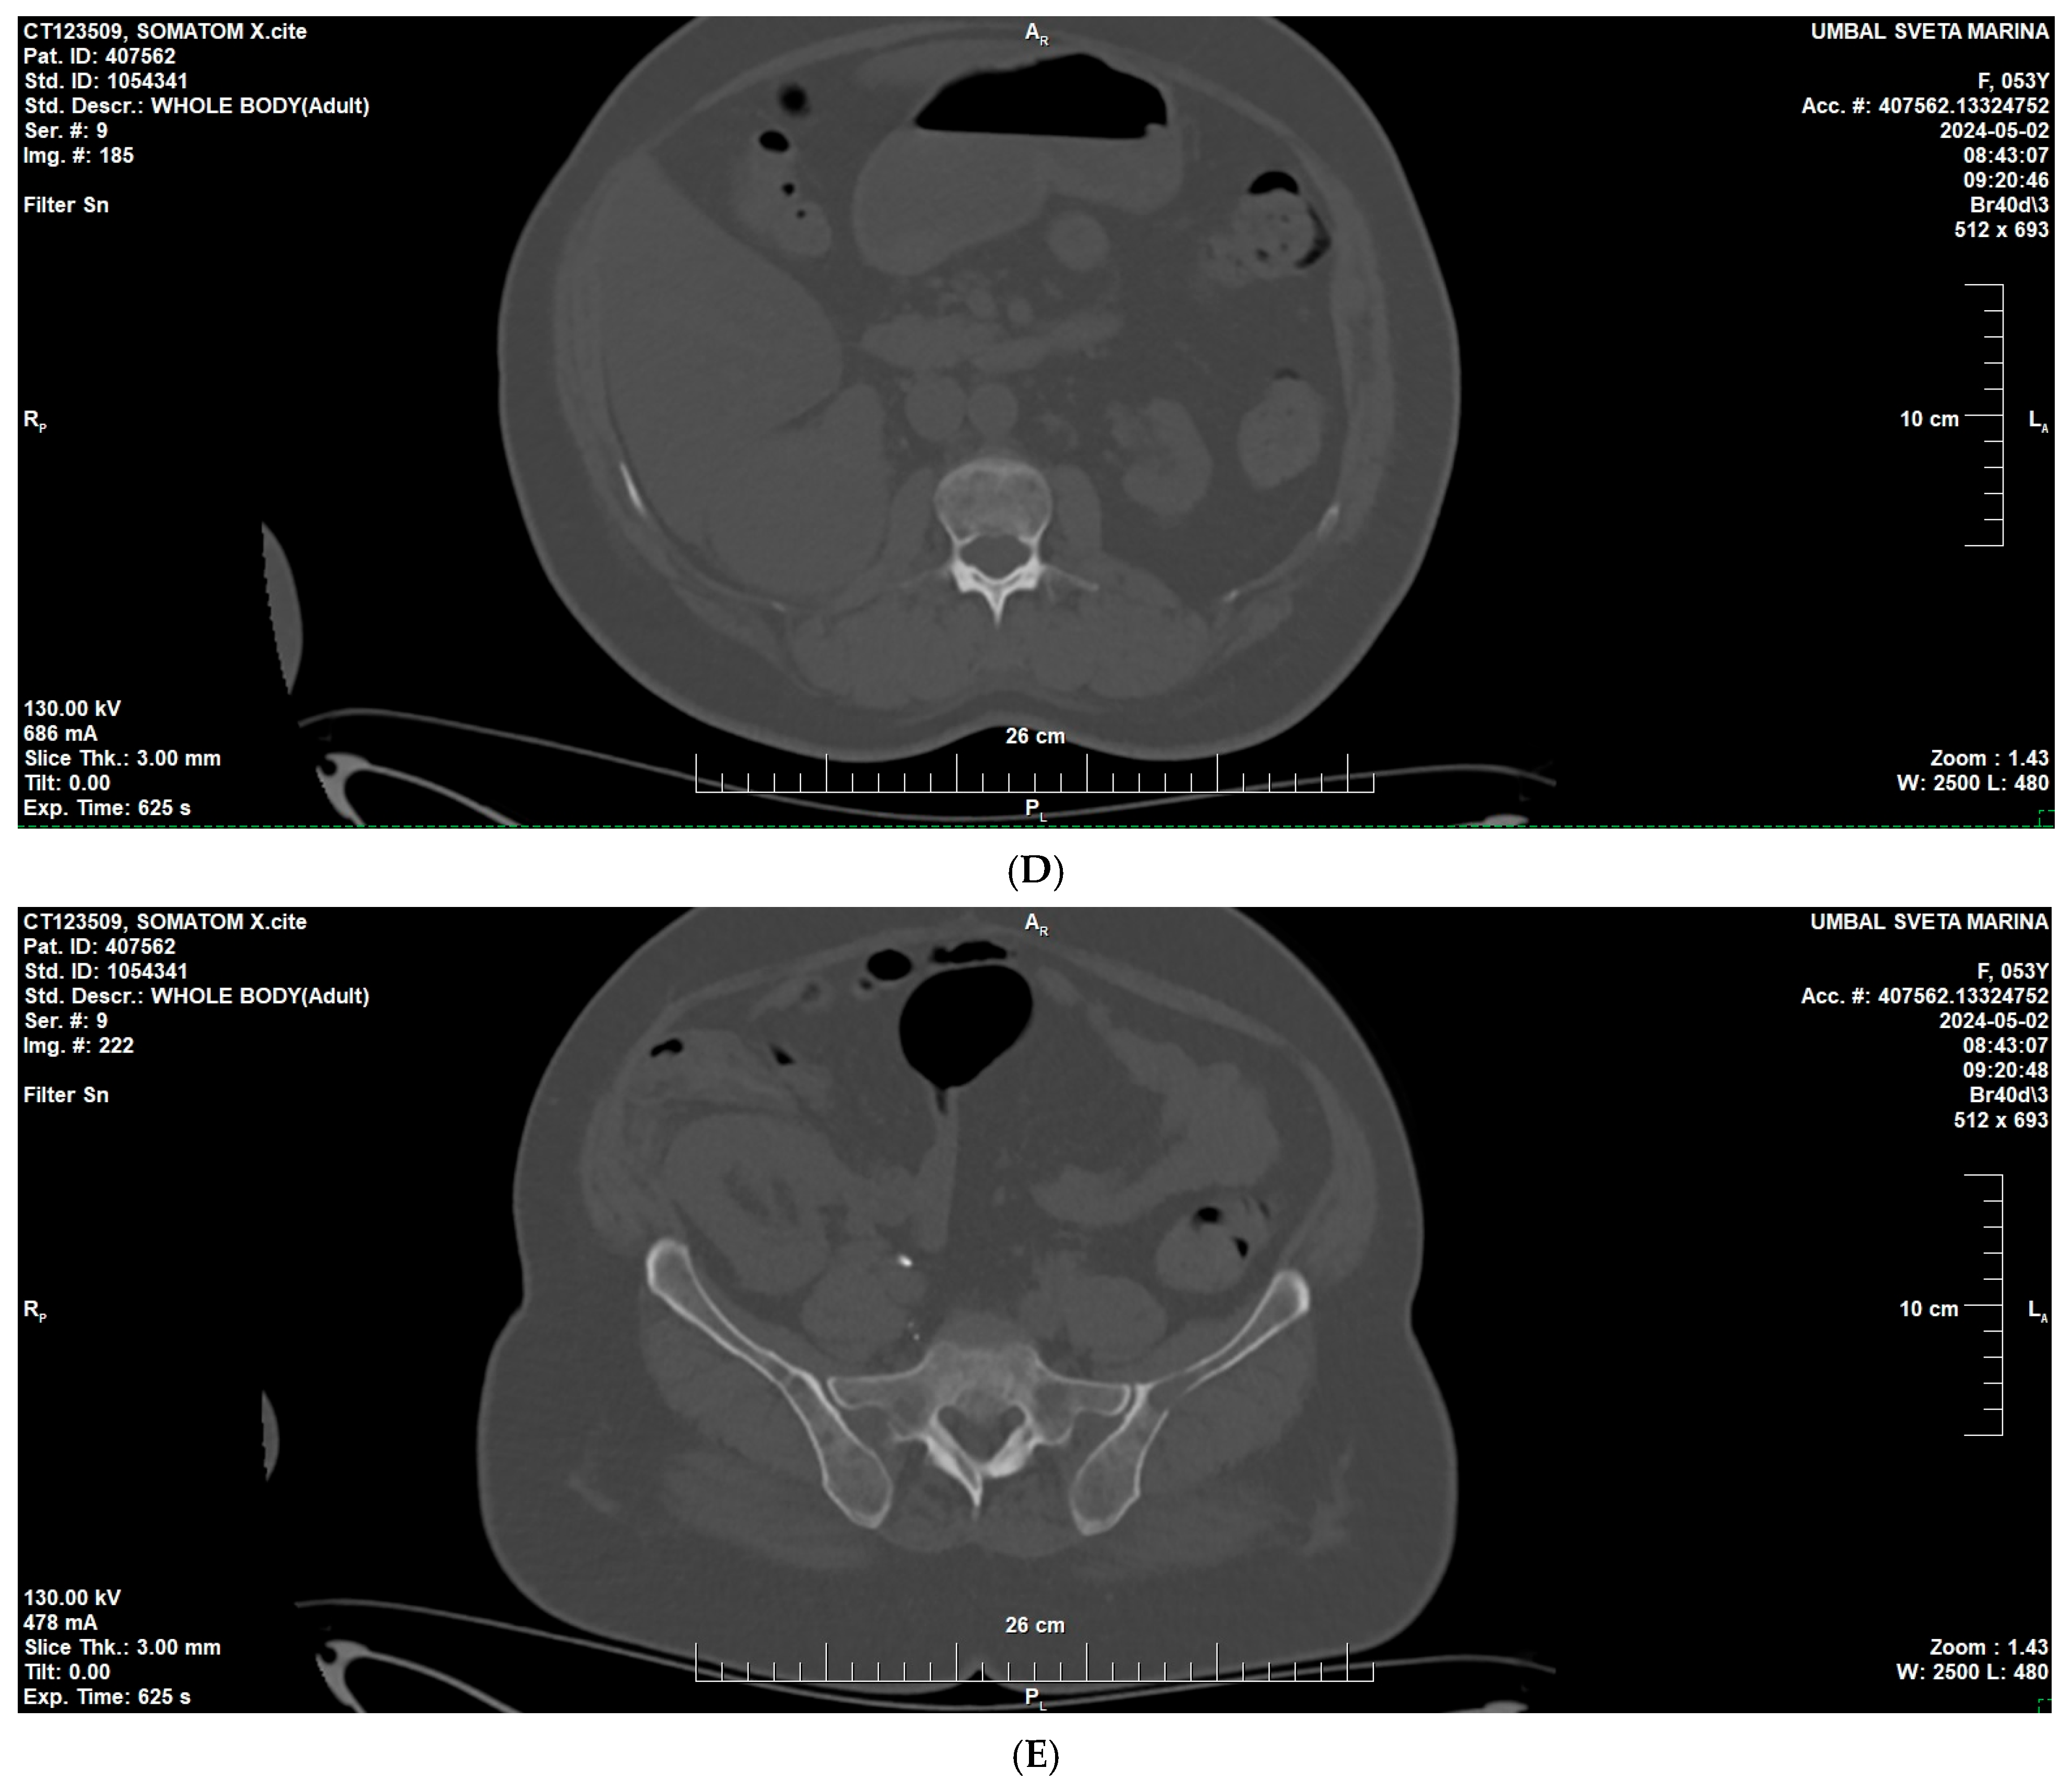

2. Case Presentation

3.2. Diagnostic Aspects